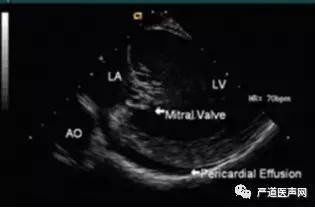

第三步,RV位置时视野,心包积液查看:以home view 为初始位置,导管打A弯,跨三尖瓣进入RV,适当推送或回撤导管,释放张力控制旋钮后,回复P/A和L/R 旋钮至中位,即mid-RV位置。二尖瓣环长轴视野:轻微顺时针旋转导管,直至二尖瓣出现在视野中,然后适当推送和回撤导管。可见图4。左室短轴视野:以二尖瓣还长轴视野为初始,导管打弯L或R弯,顺时针或逆时针旋转导管来扫描左室短轴,可见从心尖至二尖瓣的短轴视野,充分评估心包积液情况。

图4 RV位置时视野